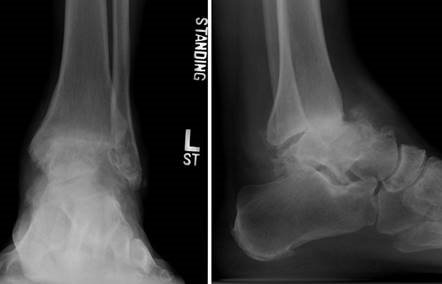

Clinical & Radiographic Imaging Archive

Clinical Image